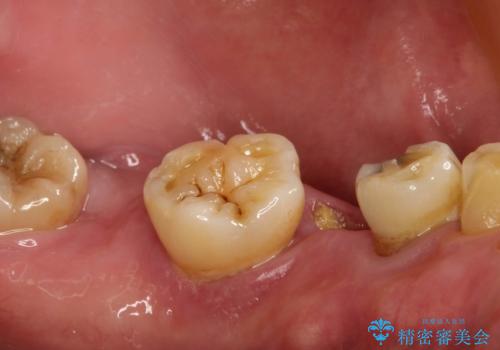

虫歯だらけ、歯周病 崩壊した口腔の再建 フルマウスリコンストラクション

- 歯周外科・インプラント・顕微鏡下根管治療などを含んだ総合的な治療を計画した。

かみ合わせの力が非常に強く、夜間の歯ぎしり・食いしばりもひどかったため、奥歯はメタルオクルーザルの設計でかぶせ物を製作しています。